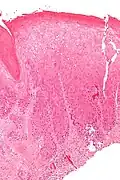

Micrograph of (classic) vulvar intraepithelial neoplasia III. H&E stain. | |

-

Micrograph of vulvar intraepithelial neoplasia III. H&E stain.